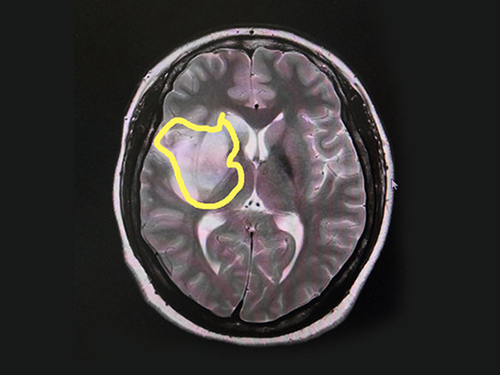

在看過(guò)患者之前做的CT影像后,有著多年臨床經(jīng)驗(yàn)的張靜波主任一眼就發(fā)現(xiàn)了其中的端倪。張靜波主任介紹,一般腦梗CT影像顯示是等密度的,而該患者影像密度不均勻,有占位效應(yīng),伴有水腫,所以一般人會(huì)認(rèn)為腦占位。但是影像學(xué)檢查顯示病灶在一條血管區(qū)域支配區(qū),再結(jié)合患者臨床,她判斷為腦血管病,只是顯示有占位效應(yīng)。

▲患者腦梗病灶區(qū)

核磁共振MRA檢查印證了她的判斷。頭顱MRI平掃+增強(qiáng)+DWI+MRA顯示患者右側(cè)大腦半球病變;MRA顯示右側(cè)頸內(nèi)動(dòng)脈、大腦中動(dòng)脈、大腦前動(dòng)脈閉塞;頸部血管彩超顯示右側(cè)頸內(nèi)動(dòng)脈未見(jiàn)血流信號(hào),雙側(cè)頸內(nèi)動(dòng)脈內(nèi)膜欠光滑、右側(cè)椎動(dòng)脈血流流速減低;生化檢驗(yàn)報(bào)告顯示:同型半胱氨酸血24.30μmol/L,而一般人正常含量一般為5–15 μmol/L。

綜合多項(xiàng)檢查結(jié)合患者臨床,趙秋華被確診為:右側(cè)頸內(nèi)動(dòng)脈閉塞引發(fā)的急性腦梗死,并伴有高同型半胱氨酸血癥。